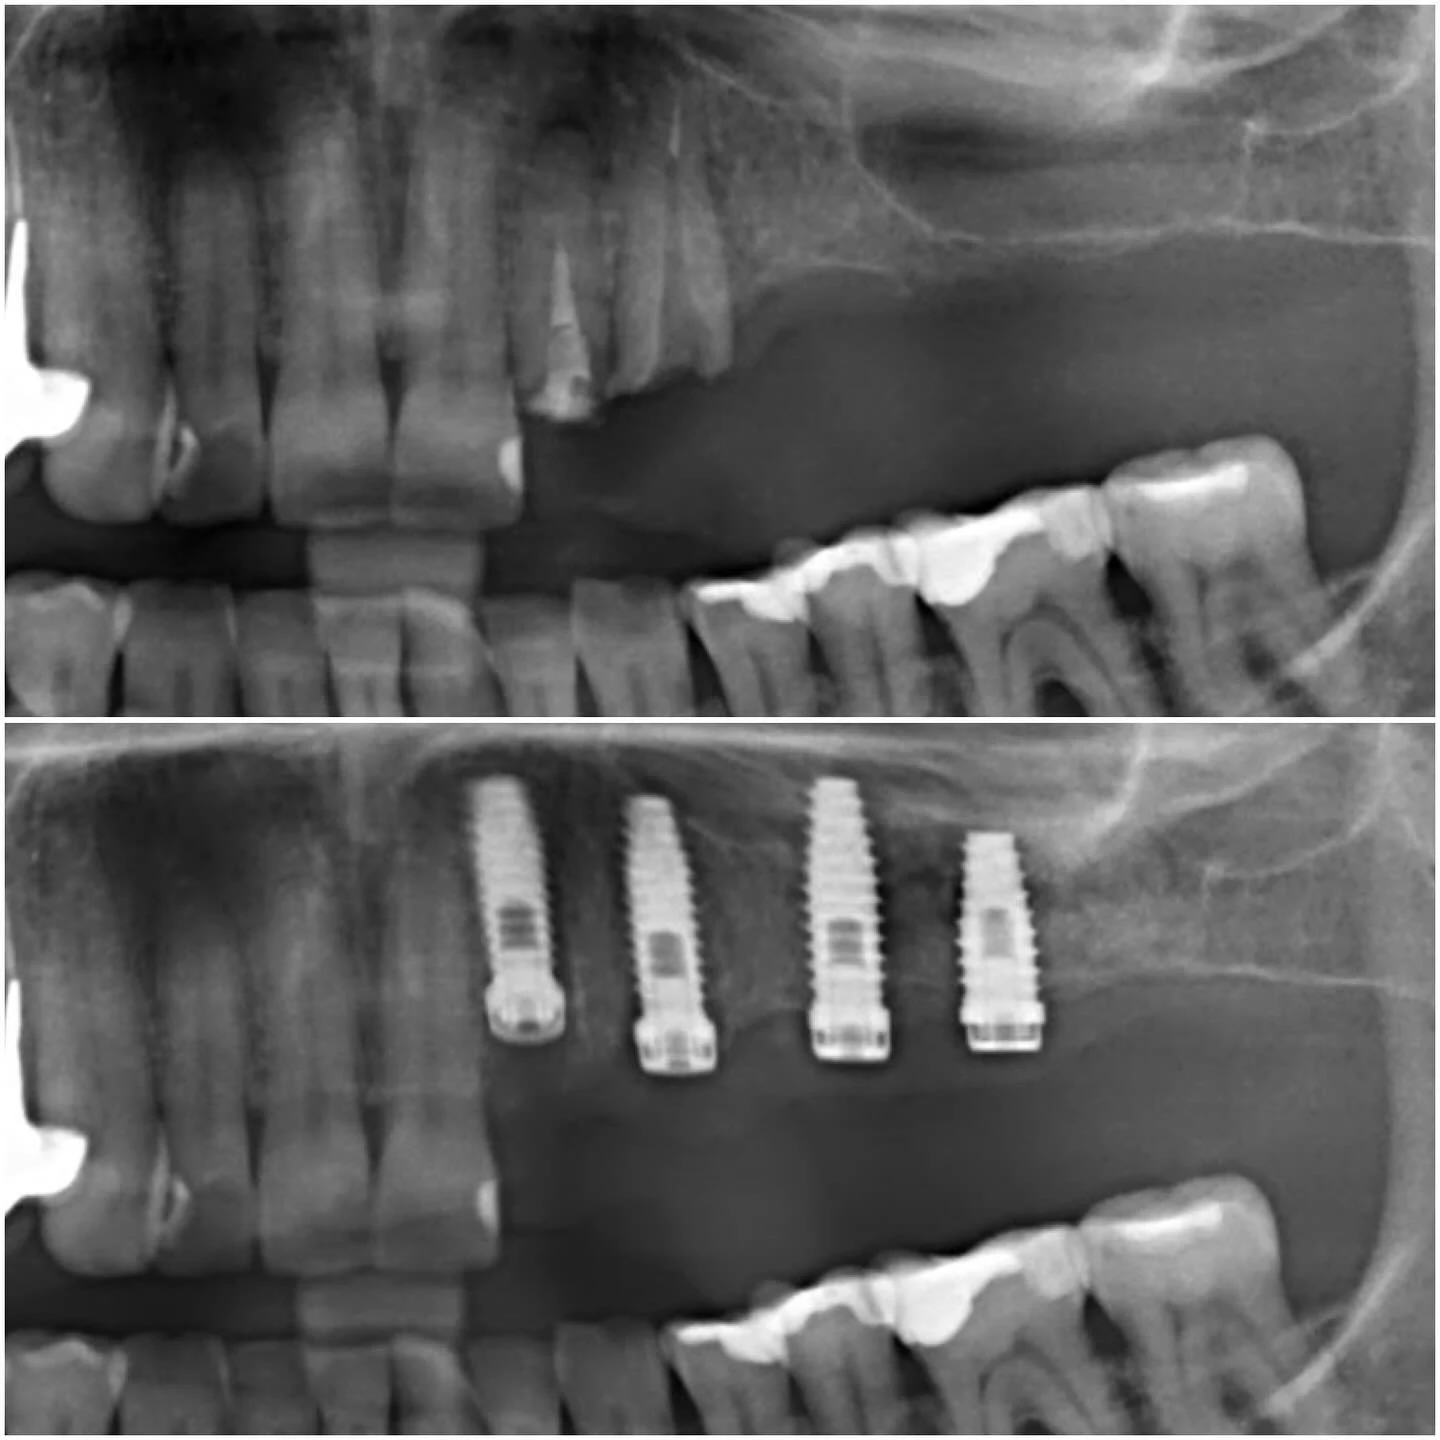

Każde leczenie w naszej klinice rozpoczynam od wnikliwej diagnostyki. W przypadkach, gdy podejrzewamy trudne warunki kostne w szczęce, absolutnym standardem jest u nas wykonanie tomografii wiązki stożkowej (CBCT). To badanie dało nam precyzyjny, trójwymiarowy obraz struktur anatomicznych pacjentki. Analiza skanów 3D potwierdziła nasze przypuszczenia: po utracie zębów doszło do znacznego zaniku wyrostka zębodołowego, a dno zatoki szczękowej – pustej przestrzeni w kości szczęki – obniżyło się tak bardzo, że ilość pozostałej kości była niewystarczająca do bezpiecznego wprowadzenia nawet najkrótszych implantów.

W tym momencie mogłam przedstawić pacjentce konkretny, bezpieczny i przewidywalny plan działania. Co najważniejsze, dzięki precyzji obrazowania 3D mogłam zakwalifikować pacjentkę do procedury jednoczasowej, która znacząco skraca całe leczenie. To właśnie technologia CBCT pozwala nam działać z taką pewnością, eliminując ryzyko i dając pacjentowi poczucie pełnego zaopiekowania.

Zabieg polegał na delikatnym uniesieniu błony śluzowej zatoki i wprowadzeniu materiału kościozastępczego. Bezpośrednio po tym, w trakcie tej samej wizyty, w przygotowane miejsce wprowadziłam implanty dwufazowe. Kluczowym warunkiem powodzenia takiej zintegrowanej procedury jest uzyskanie tzw. stabilizacji pierwotnej implantu w kości własnej pacjentki.

Dzięki naszemu doświadczeniu i precyzyjnemu planowaniu na podstawie tomografii CBCT, osiągnięcie tej stabilności jest w naszej praktyce standardem. Oznacza to, że implanty mogą bezpiecznie zrastać się z kością w tym samym czasie, w którym wszczepiony materiał przekształca się w nową, pełnowartościową tkankę kostną.

Po okresie gojenia wykonaliśmy kontrolne badanie CBCT, które potwierdziło wspaniały rezultat regeneracji kości. Przyszedł czas na wszczepienie implantów dwufazowych. Są to tytanowe wszczepy, które po wprowadzeniu w kość zostają całkowicie zaszyte pod dziąsłem na okres osteointegracji, czyli zrastania się z kością. To klasyczna i niezwykle dobrze udokumentowana naukowo metoda, która w skomplikowanych przypadkach daje największą pewność sukcesu.